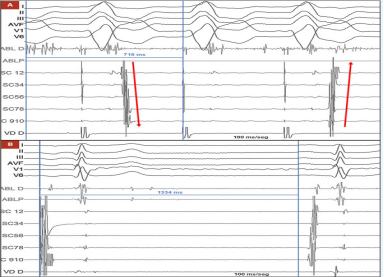

基于电生理检查结果,介入团队决定行射频消融术,而非直接置入起搏器,具体过程如下:消融路径:穿刺右侧股动脉,将消融导管(ABL)通过主动脉后入路推进至二尖瓣环(左隐匿性旁路常位于二尖瓣环附近);靶点定位:在右心室起搏期间绘制逆行心房激活图,于二尖瓣环前外侧区域发现 “融合VA间期” 及可能的通路电位,此处心房活动最早出现,确定为消融靶点;消融实施:采用功率控制射频(35W)进行消融,0.7s 后即观察到旁路传导中断,心房激活模式从 “偏心型” 转为 “同心型”(提示旁路逆传功能消失,图3A);疗效验证:消融后等待30分钟,多次尝试刺激均未再诱发出心动过速,提示消融成功;

(图3A,图3B)

窦房结功能评估:消融术中常规行窦功能测试,程序性心房刺激后窦房结恢复时间(SNRT)为1334ms(正常值 < 1500ms,图3B),表明窦房结功能正常,不存在原发性窦房结功能障碍。